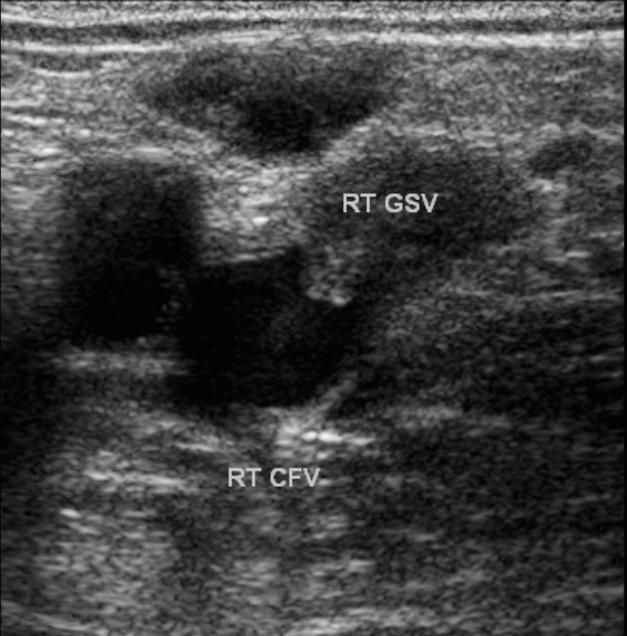

Endovascular treatment of varicose veins is not without complications. The most common complications are not severe and include local bruising and soreness of the overlying skin. More severe complications include deep vein thrombosis and burns. In a series of 73 limbs treated with radiofrequency ablation of varicose veins, DVT developed in 12. The following image shows a greater saphenous vein post ablation with the thrombosis extending proximally into the common femoral vein: